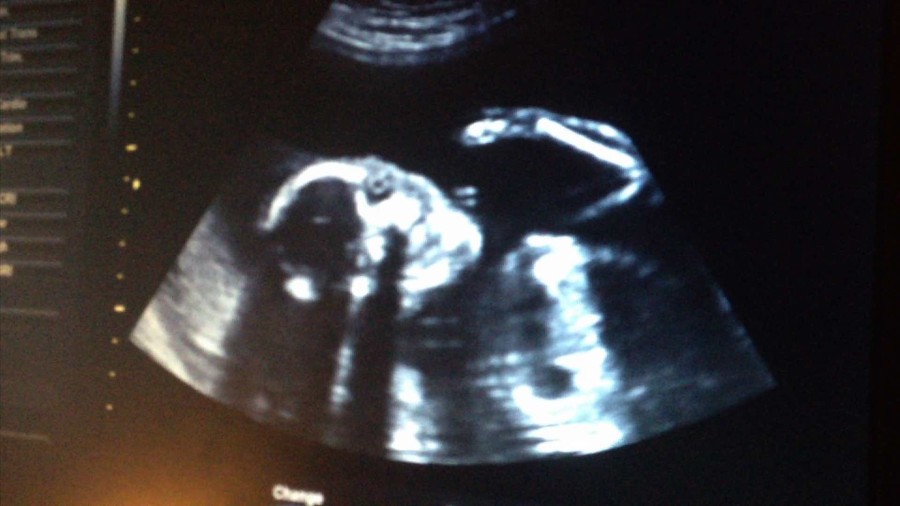

Im Zentrum der Ausstellung Point of No Return im Heidelberger Kunstverein steht die gleichnamige Videoarbeit von 2015. Angelehnt an die Struktur des Reiseberichts sampled Antje Engelmann dokumentarisches Filmmaterial aus ihrem privaten Archiv und dem Internet mit eigenen Texten zu einem vielschichtigen filmischen Essay: Neben ihrer eigenen Stimme sind Audio-Aufnahmen von der »Golden Record« zu hören, die die NASA 1977 mit den Raumsonden Voyager 1 und 2 als Botschaft für Außerirdische ins All sandte. Der Künstlerin begegnen auf einer Reise von New York nach Los Angeles die Naturgewalten der Prärie, Vögel und Menschen: Da ist der Biologe und Gentechniker, der sich die genetische Entschlüsselung und Wiedererweckung der im 19. Jahrhundert von den Siedlern ausgerotteten Wandertaube zur Aufgabe gemacht hat. Oder der Ex-Bodybuilder vom Muscle Beach in Venice, der mit seinem Papagei gerade einem tödlichen Blitzgewitter entkommen ist und von den Weiten des Kosmos berichtet. Und der Beat Poet, der von Indianern, psychoaktiven Kakteen und schamanistischen Ritualen erzählt und in seinem letzten Roman ebenfalls von Wandertauben schreibt. Und da ist sie selbst als werdende Mutter. Auf ihrer Reise durch die Kulturgeschichte des Westens der USA stößt Antje Engelmann immer wieder auf ikonografische Bilder verschiedener Wissensformen und im weitesten Sinne auf anthropozäne Prozesse: Die Utopien der Gegenkultur, das erste fotografische Bild der »ganzen« Welt (The Blue Marble), Martha, die letzte Wandertaube, der Kuksu-Tanz und physische Spannungen der Erde tragen durch den Film, der sich allen gängigen Genres widersetzt. Point of No Return ist ein Film über Auslöschung und Wiederbelebung, über Tod und Geburt. Die vielschichtige Montage von Material und Entwurf macht ihn zu einer oszillierenden Suche vom Mikrokosmos zum Makrokosmos und wieder zurück. (Text. Susanne Weiß)